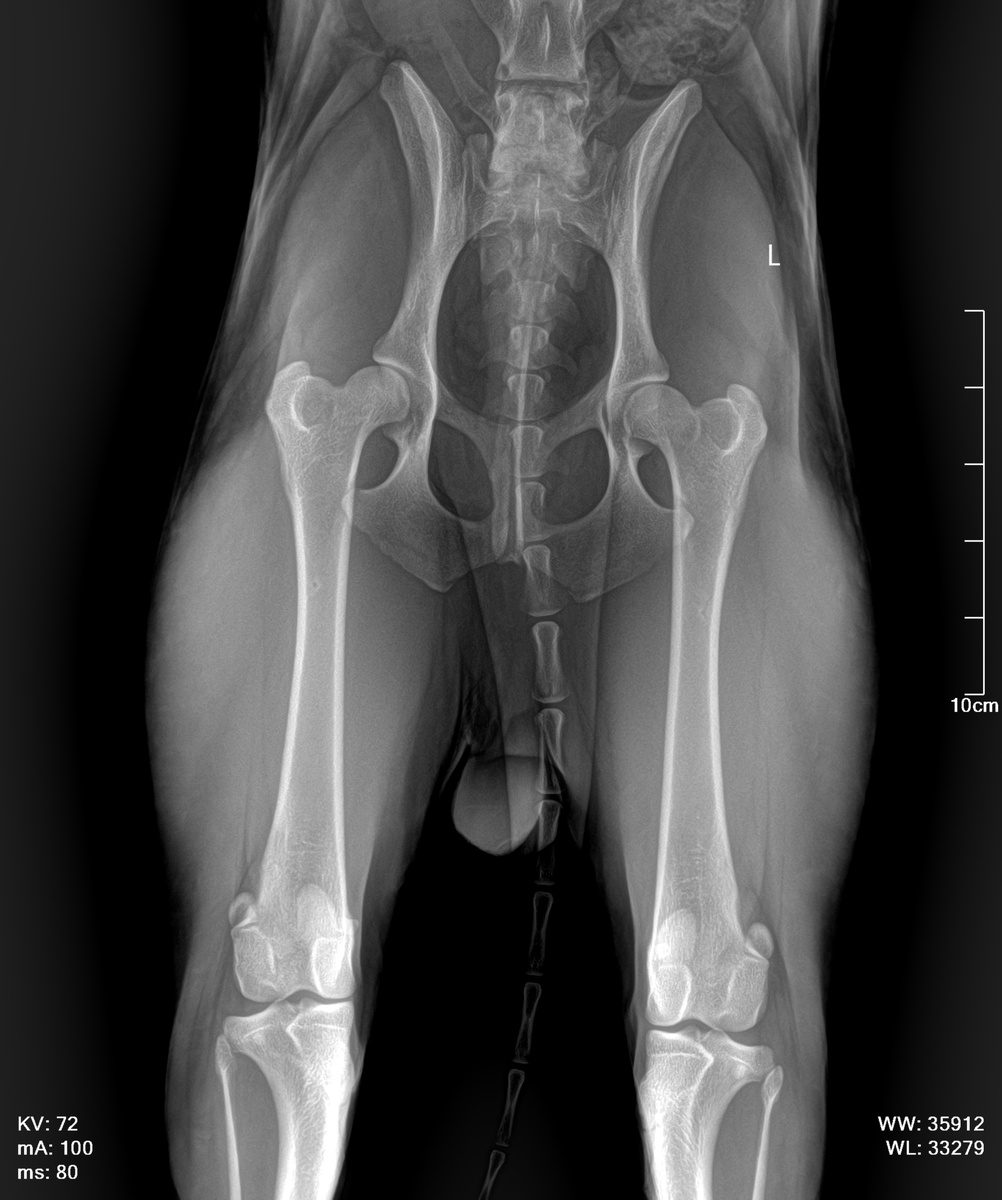

Дисплазия может быть установлена посредством рентгена или КТ (в определенных случаях). Для того, чтобы получить правильную картину, собака должна быть правильно уложена для рентгена под седацией.

Степени дисплазии ТБС принятые в Европе и России:

А, B, C, D, E,

А и В - отсутствие дисплазии. Степень В дается тем собакам, у которых суставы хорошие, но не идеальны на 100%

С – самый легкий вариант дисплазии. При ней, сам сустав в порядке, склонен к небольшому стиранию и есть небольшой артроз или артрит.

Д – сустав не в порядке и имеют сильный артрит или артроз. Собаки с Д в Европе и России не допускаются в разведение, в связи с тем, что процент генетики в дисплазии ТБС есть.

Е – сильнейшая дисплазия, то есть вертлужная впадина практически не развита или разрушена и имеется сильнейший артроз или артрит.